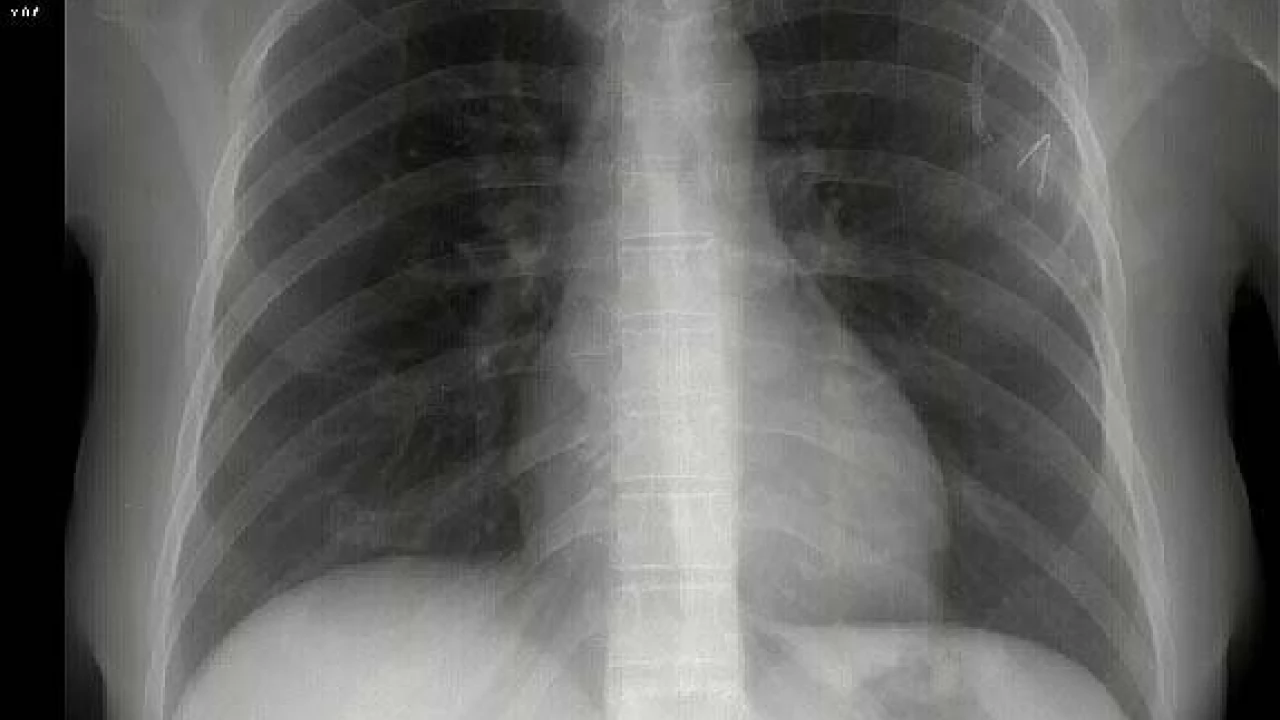

Pracownia Rentgenodiagnostyki w Tczewie zaprasza mieszkańców miasta na bezpłatne badania radiologiczne klatek piersiowych (duże zdjęcie rtg płuc) w ramach zorganizowanego przez Urząd Miejski w Tczewie programu profilaktycznego na 2010 roku.

Dodajmy, że to nie pierwsza tego typu akcja w naszym mieście. W ubiegłym roku ponad 6 tysięcy mieszkańców grodu Sambora skorzystało z profilaktycznych badań rentgenowskich. Dzięki nim wykryto 8 świeżych zmian gruźliczych, 12 zmian pogruźliczych, 31 zmian typu - guz płuca oraz zmiany meta, 44 zmiany pneumoniczne (zapalne) i 66 zmian o charakterze łagodnym w płucach. Badania pozwoliły również na znalezienie 208 zmian w układzie sercowo-naczyniowym, w tym powiększeń sylwetki serca oraz wad serca. Ponadto stwierdzono 79 zmian kostnych, w tym 2 skoliozy kręgosłupa piersiowo-lędźwiowego.